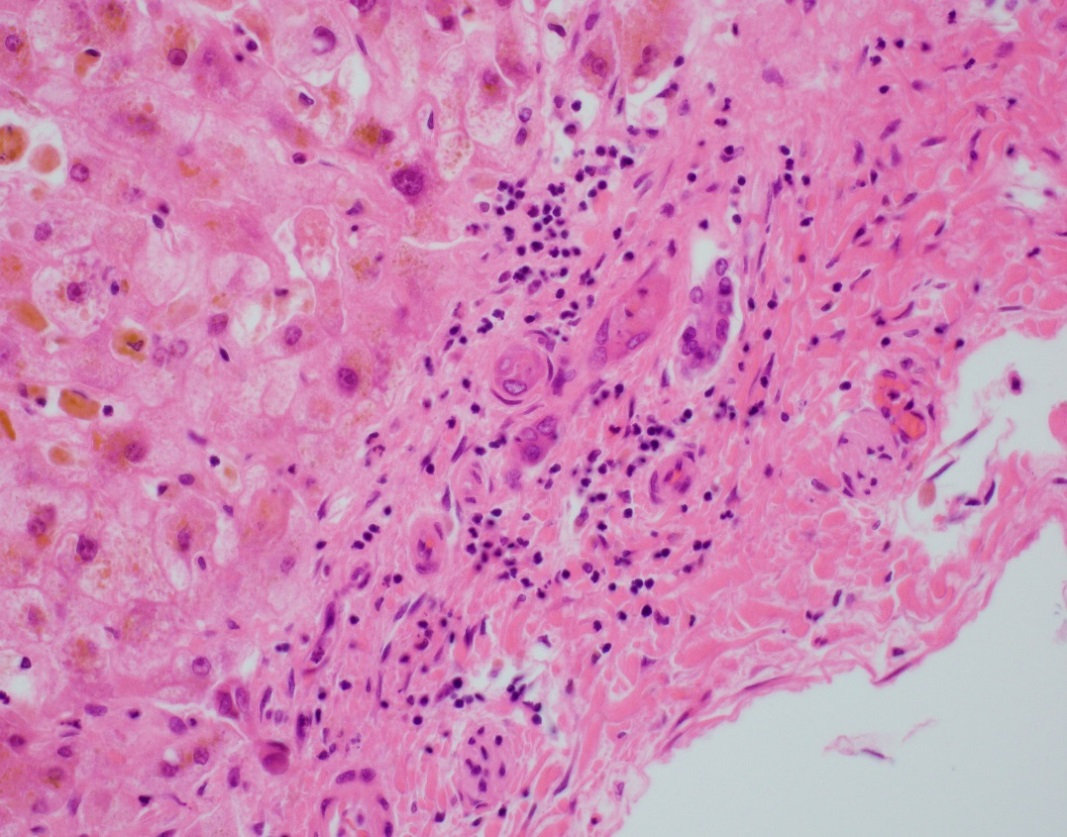

The explant showed submassive hepatocellular necrosis with marked cholestasis, and markedly dystrophic changes in bile duct epithelium in the portal tracts, but there was no ductopenia. Ductular reaction was conspicuously absent. The portal tracts showed mild chronic inflammatory infiltrate, associated with mild focal endothelialitis, and reduced number of small arterial branches. Medium-sized bile ducts showed periductal fibrosis along with dystrophic epithelial changes. Large bile ducts showed foci of intraepithelial lymphocytes, and focal reactive changes. There was central perivenulitis, with foci of lobular microabscesses. There was no foam cell arterial lesion, fibro-muscular intimal thickening, or inflammatory infiltration of muscular arteries. Trichrome stain highlighted fine perisinusoidal fibrosis, extending to portal tracts, but there is no bridging fibrosis. Reticulin showed a largely preserved architecture. A cytomegalovirus immunostain was negative.

Histologic features of chronic rejection and ischemia.

The histologic diagnostic features for CR include presence of dystrophic bile duct epithelium, bile duct loss, and foam cell obliterative arteriopathy. Some cases of late CR have also been reported to show chronic hepatitis-like changes. As has been described with acute presentations of chronic rejection, this case showed prominent inflammatory infiltrate, including endothelialitis and perivenulitis, which initially raised the histologic concern for acute rejection. The patient however remained unresponsive in spite of marked immunosuppressive therapy, and over time in the course of a few months, the inflammation reduced (reflected by the decrease in liver enzymes) whereas the bile duct dystrophy became more conspicuous, characteristically with no ductular reaction. With these clinical and histologic features, this was deemed as an unusual course of CR.